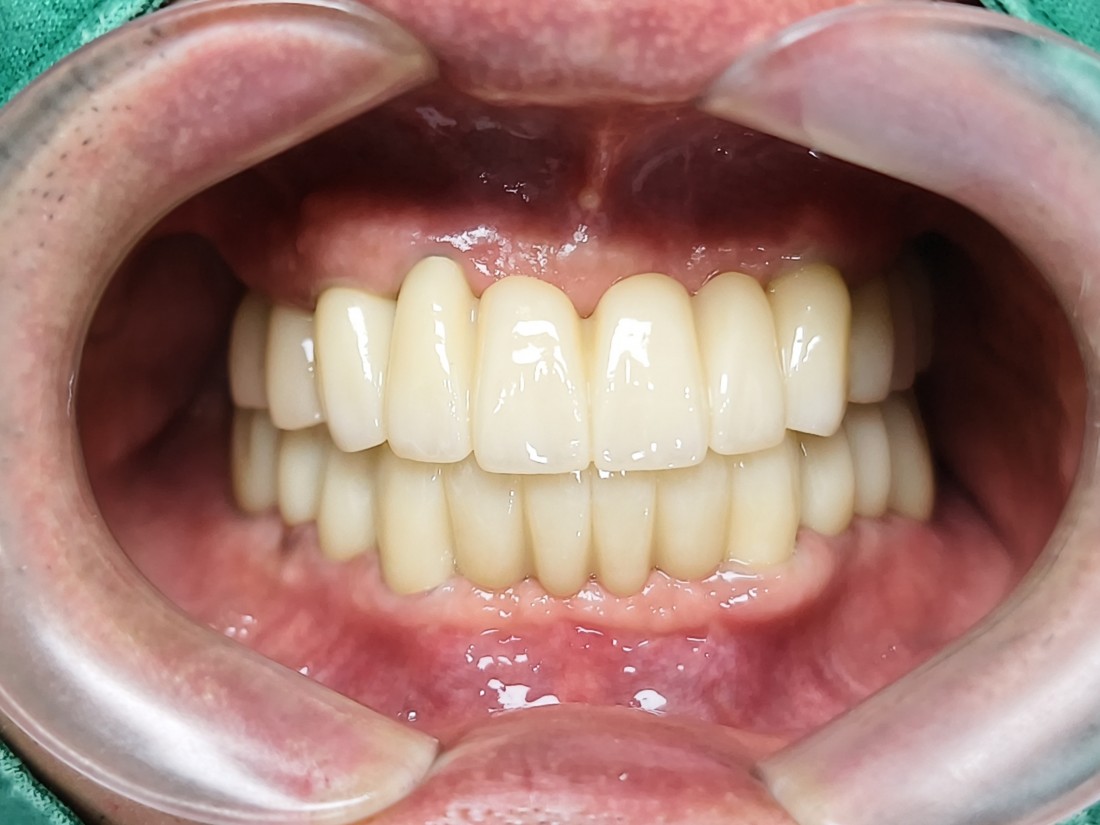

광주 전체임플란트 치과의 약속

1. 안아프게

2. 예쁘게

3. 잘 씹어지게

무엇보다도 전체임플란트 중에서

특히 앞니임플란트가

자연스럽고 예쁘게 완성이 되는지

많이 걱정하실텐데요.

광주 전체 임플란트 치과는

4층 자체 치아기공소를 운영하여

보철물 퀄리티를 최상으로 유지합니다.

자연치아보다 더 자연스럽게,

더 잘 씹어질 수 있도록

심미적인 요소와 기능적 요소를

모두 고려하여 제작하고 있으며

불편함이 생기시면 바로 수정이 가능하기 때문에

번거로움 없이 광주 전체임플란트를

완성할 수 있습니다.